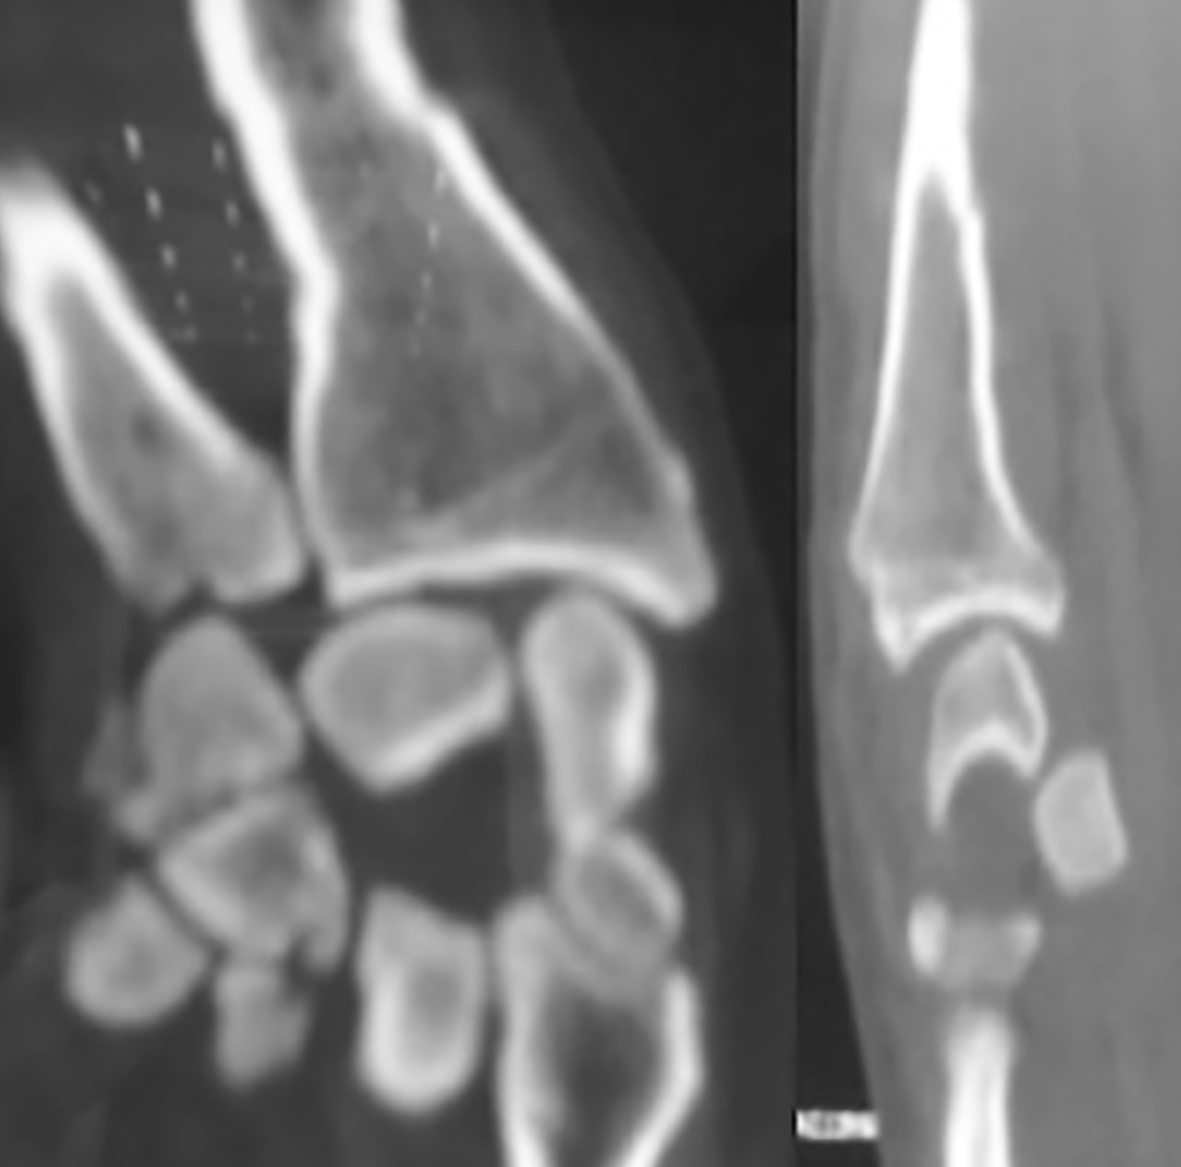

Paciente de sexo masculino, de 26 años, diestro, sin antecedentes personales a destacar, que fue embestido por automóvil mientras manejaba su moto. El paciente presentó una lesión encefálica focal que requirió tratamiento médico. Estuvo en coma 20 días, aparentemente sin otras lesiones. Luego, ya con vida de relación retomada, el paciente relató dolor e impotencia funcional de su mano derecha. Tumefacción y dolor a la movilización (pasiva-activa) y a la prehensión en el examen físico. Las radiografías y el TC mostraron una luxación volar de hueso grande de mano derecha (Figura 1) asociada a fracturas de la base del tercer metacarpiano y de hueso piramidal, ambas sin desplazamiento (Figura 2). A las 8 horas de establecer el diagnóstico se realizó una reducción abierta por vía palmar con fijación interna, con alambres de Kirchner de 1,5 mm, (Figura 3). Se agregó un mini fijador externo para proteger la estabilidad de la osteosíntesis del carpo y manejar las partes blandas lesionadas. No se realizó reconstrucción ligamentaria.

Figura 2: Cortes de TC coronal y sagital que evidencian luxación palmar de hueso grande asociada a fractura del piramidal y base del segundo y tercer metacarpiano.